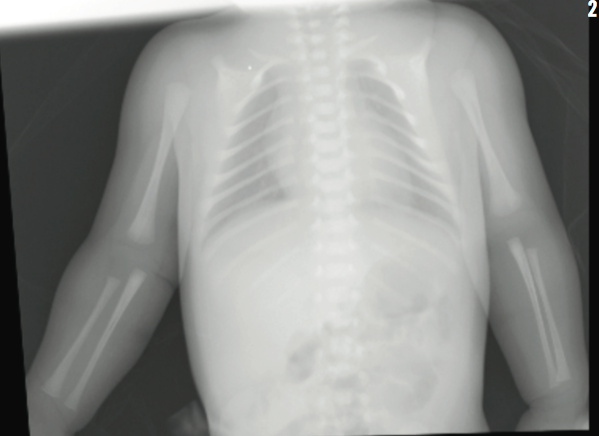

The results of transfontanelle ultrasonography of the head were unremarkable, and radiography of the skull revealed thinning of the calvarium, frontal bossing, and increased anteroposterior diameter of the skull. Calcium, phosphorus, alkaline phosphatase, and vitamin D serum levels were within reference ranges. Skeletal survey revealed absence of the lateral two-thirds of each clavicle, nonossification of pubis, and unremarkable positioning of the hip joints. The neonate was discharged home on day 4 of life.

The girl is now 2 years old. Her skull bones are still underdeveloped but are progressively getting better. Her height is at the 50th percentile for her age. Her dentition is appropriate for her age, and her repeated hearing tests all have been normal. She has developed progressive infantile scoliosis for which she is being managed with serial casting.

Radiographic findings of cleidocranial dysplasia include delay in closure of the skull fontanelles, hypertelorism, partial or complete absence of clavicles, and lack of ossification of the pubis.2,6 None of the primary clinical findings have serious sequelae.